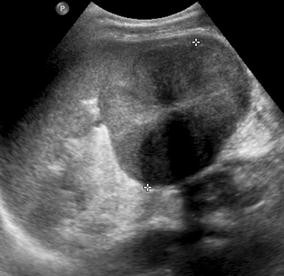

Fig. 3